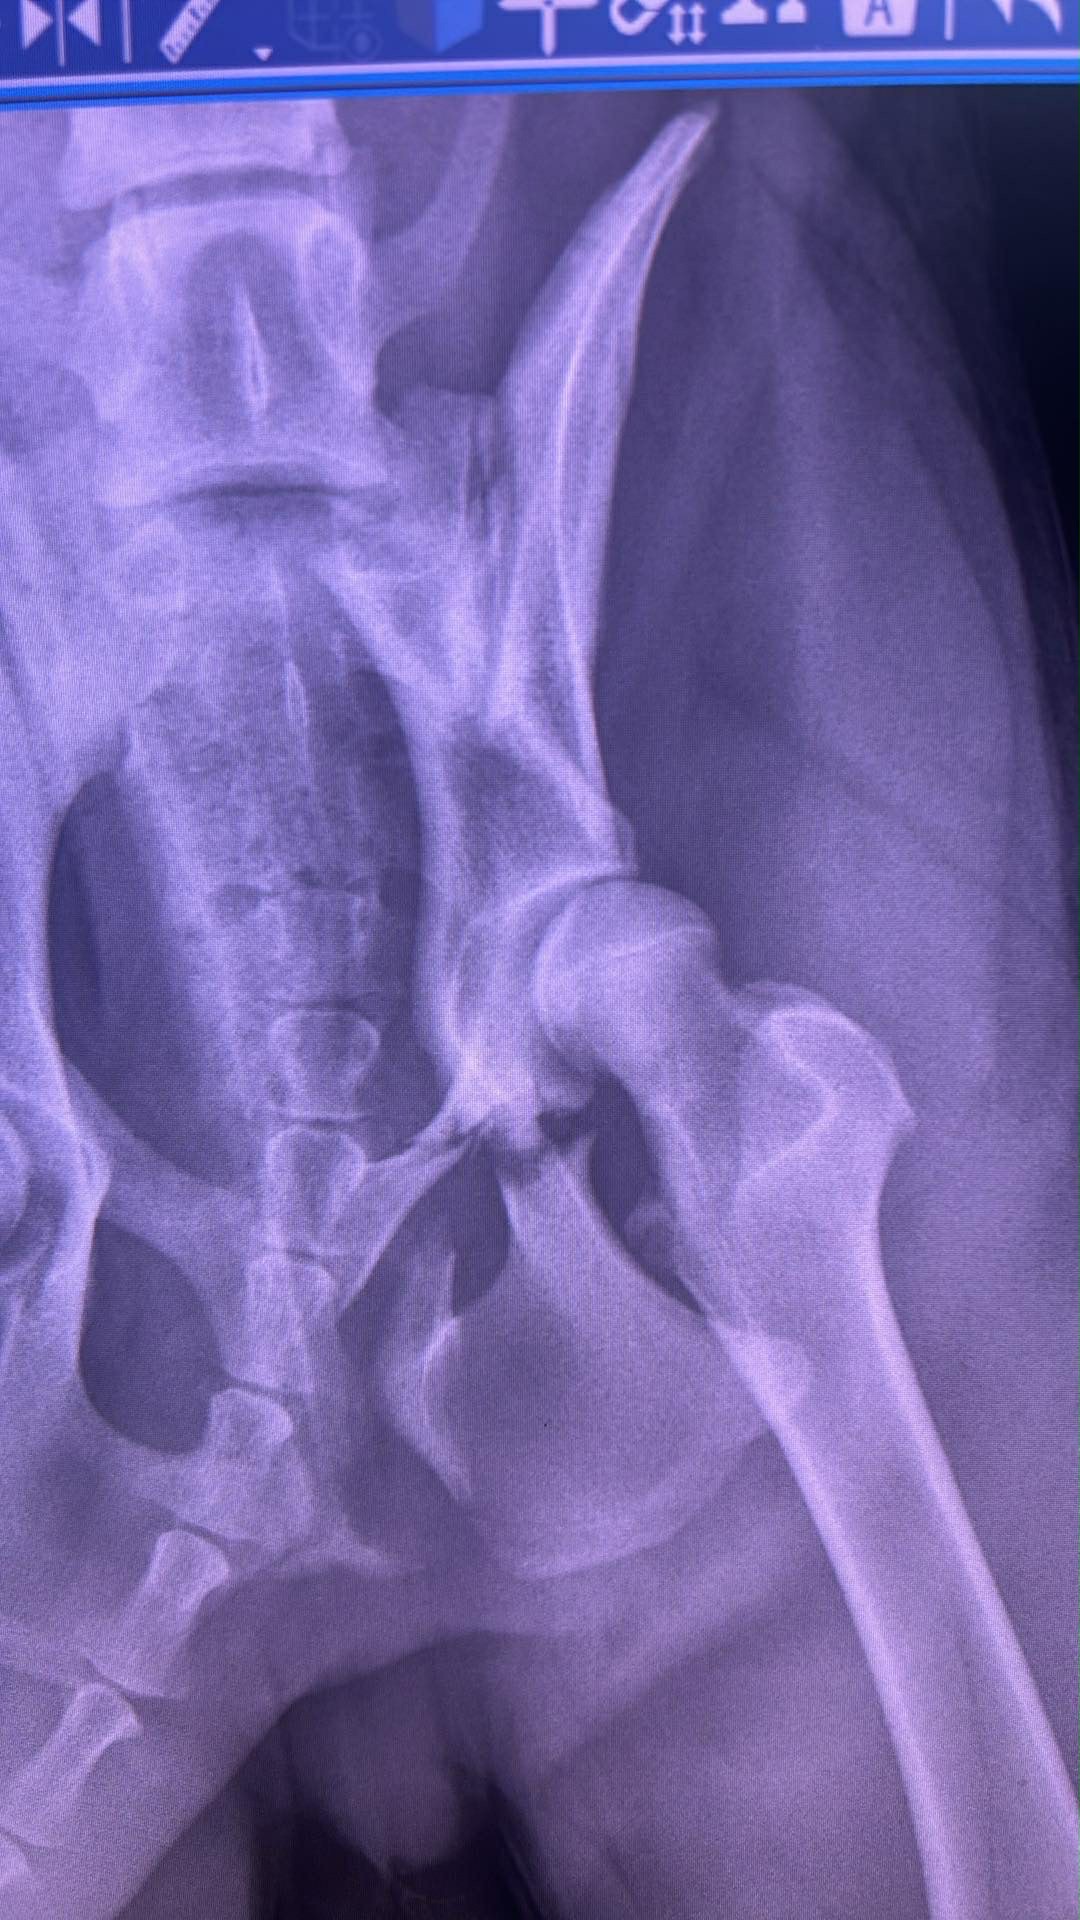

Rocco has a pelvis injury — broken in two places. We were given a few options:

➡️ Let it try to heal on its own (but one of the breaks has a splinter that could puncture his bladder or worse)

➡️ Or go through surgery with a plate and screws to give him the best chance at healing correctly.